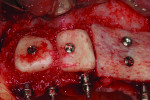

Placement of four NDIs (1.8 mm x 14 mm) (ANEW®, Dentatus, www.dentatus.com) guided by a CAD/CAM surgical template (iGuide, Midwest Dental Arts, www.midwestdentalarts.com) was performed without flap elevation (Figure 4 and Figure 5). A single 1.4-mm pilot drill (CePo®, Dentatus) was used to prepare the osteotomy under copious irrigation at 1000 RPMs. The four NDIs were subsequently inserted at low speed (30 RPM) in position Nos. 7 through 9 and 12 (Figure 6 and Figure 7). Primary stability was tested with a torque driver and found to be sufficient for immediately loading the implants. Following placement of the NDIs, the patient’s provisional restoration was connected chairside.

Five months later, the block grafts appeared well integrated, and no signs of inflammation or bone resorption were noted. Two of the four NDIs (Nos. 7 and 12) were retained as planned and supported the provisional, while the other two (Nos. 8 and 9) were removed and replaced with three standard-diameter implants (3.5 mm x 13 mm) (Zimmer Dental) in sites Nos. 8, 9, and 11. Healing abutments were connected to these three implants (Figure 12). Due to a partial resorption of the allogeneic block graft, implant No. 11 was placed slightly more apical than Nos. 8 and 9, and a guided bone regeneration procedure was performed simultaneously using particulate allogeneic graft (Puros Cancellous Particulate Allograft) and a resorbable collagen membrane (Bio-Gide). The flap was sutured with absorbable 4-0 chromic gut sutures (Ethicon). The augmented area was submerged while implants Nos. 8 and 9 and their healing abutments were left exposed (Figure 13). The provisional was relined with TrueRepair to close the access holes through which NDIs Nos. 8 and 9 had been connected to the restoration and to cover the two non-submerged healing abutments. At this stage, the provisional remained connected and supported only by two NDIs (Nos. 7 and 12).